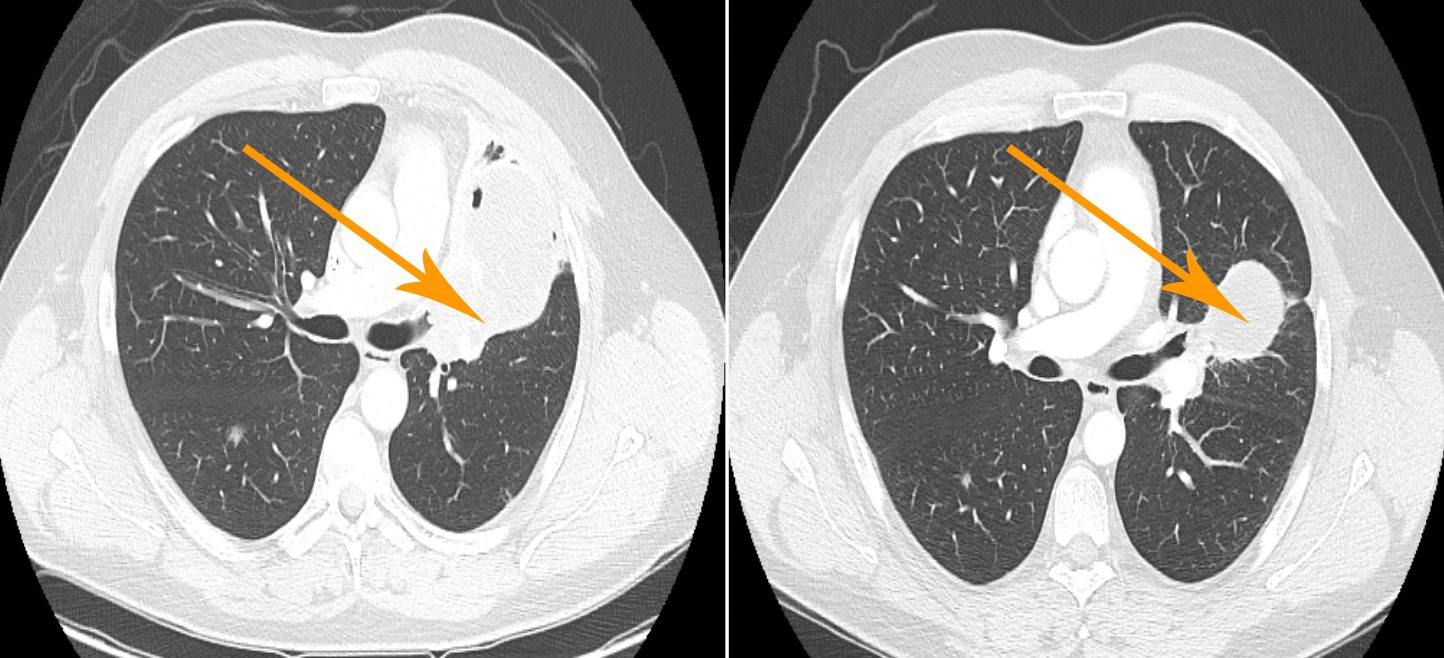

Por lo tanto, el Dr. Kuerer y sus colegas recurrieron a la biopsia con aguja fina guiada por imágenes, mediante la cual se inserta en la mama una aguja que penetra en la región tumoral bajo control ecográfico o mamográfico y se la hace girar para obtener alrededor de una docena de muestras de diferentes sitios. Los investigadores realizaron biopsias preoperatorias guiadas por imágenes en 40 pacientes con cáncer de mama triple negativo o cáncer de mama positivo para HER2 después de la terapia sistémica neoadyuvante y compararon los resultados con los del examen tradicional de las muestras quirúrgicas de las pacientes.

Durante la terapia neoadyuvante, que por lo general dura de 5 a 6 meses, las pacientes son monitoreadas con estudios de imágenes mamarias, lo cual es el procedimiento estándar. Para que las pacientes sean elegibles para la biopsia guiada por imágenes y tengan la posibilidad de prescindir de la cirugía, la lesión mamaria en la imagen final debe ser de 2 cm o más pequeña.

“Elegimos ese tamaño porque cuando la anomalía se reduce hasta ese punto, podemos obtener un muestreo verdaderamente bueno del área con las biopsias por punción, casi tan bueno como con la cirugía misma”, dijo el Dr. Kuerer.